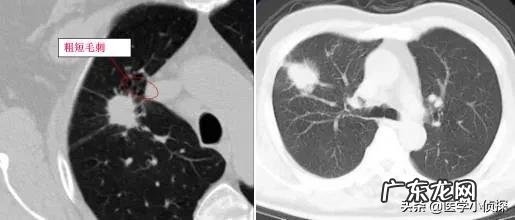

而且拍片发现肺结节 , 本身不能说我们得了什么病 , 因为肺结节只是我们影像学上的一种表现 , 并不代表这个结节具体会是个什么东西 。只是对于我们正常人来说 , 不应该有结节 , 因此结节的出现肯定代表我们的肺部有病变 , 但具体它是什么 , 是良性的 , 还是恶性的 , 需要进一步的来区分 。只不过 , 一般情况下 , 在影像下我们统称这些都叫肺结节 。

而同样 , 我们既不知道它是个什么东西 , 也不知道它是怎么来的 , 有一部分人可能跟我们的肺部炎症有关;而有一部分可能与肺结核有关 , 但具体一个人为什么会长肺结节 , 目前并没有研究清楚 , 这就导致了很多在看到自己体检报告肺部有结节时候会有点恐慌!

假如你胸部CT检查出肺结节 , 重点关注报告单上这些内容 , 基本上不用过于担心肺结节最后会发展为晚期肺癌!